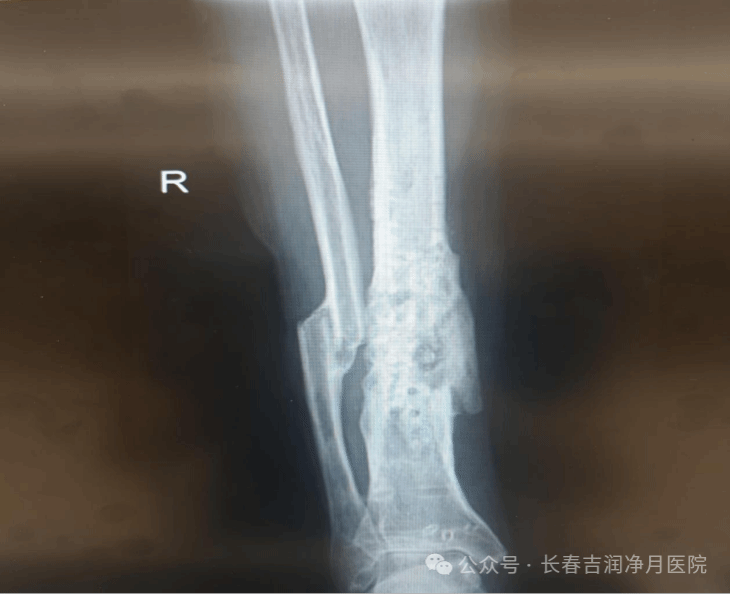

(2020年10月,外院做完手术的右胫腓骨正侧位复查片)